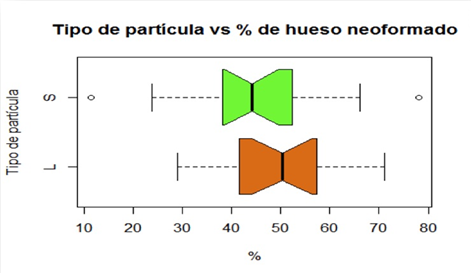

Para el análisis histomorfométrico, se evaluaron las imágenes distinguiendo el tejido óseo vital de neoformación, el tejido blando no mineralizado (médula ósea, tejido conjuntivo, etc.) y el material de injerto. La diferenciación de hueso vital de neoformación, con respecto al material de injerto y otras estructuras, se realizó evaluando las características de hueso con las tinciones utilizadas y la presencia de osteocitos.El material de injerto se identificó por la ausencia de osteocitos. Se midió el área total del cilindro óseo y subsecuentemente las diferentes áreas mencionadas anteriormente, obteniéndose un valor expresado en porcentajes.Para este análisis, se realizó la identificación de las áreas por dos observadores ciegos calibrados. Para cuantificar el porcentaje de las diferentes áreas se trabajó con el software de edición de imagen Raster Adobe Photoshop CS5.Del área total del cilindro óseo se substrajeron los espacios en blanco, que correspondían a zonas de contracción del tejido consecutivas al procesamiento histológico. Los demás tejidos fueron identificados con un color diferente y medidos sus porcentajes por el software de edición de imágenes. Los porcentajes de cada tejido y del material de injerto se expresan en la siguiente tabla. (Fig. 6)

El procesamiento estadístico de estos resultados fue realizado en la Unidad de Estadística de la Facultad de Odontología. Al aplicar la prueba de los rangos con signo de Wilcoxon(22) se observó un valor p de 0.1454. Tomando un nivel de significación de 0.05, no existe diferencia estadísticamente significativa para descartar la igualdad de medianas entre ambas poblaciones. (Fig. 7)

En el diagrama de cajas se observa que los intervalos de confianza para la mediana se superponen, lo que no permite afirmar que las medianas de ambos grupos difieren.

Los resultados de este estudio se encuentran en línea con trabajos previos que utilizaron como osteoconductor para la elevación sinusalel HMBD. La utilización de los dos tamaños de partículas utilizadas en este estudio parece no influir en el resultado en cuanto a la formación de nuevo hueso. Chackartchi et al. en 2010 no encontraron diferencias cínicas e histológicas entre las dos presentaciones de HMBD al estudiarlas en elevación sinusal, siendo ambas exitosas17. Los resultados obtenidos en el presente estudio, confirman que se encuentran altas tasas de neo-formación ósea, independientemente del tamaño de partículas utilizado L y S (47.2% y 42.6% respectivamente).

El estudio demostró que no existe diferencia estadísticamente significativa en la cantidad de nuevo hueso formado, en relación al tamaño de las partículas utilizadas. Por este motivo sería recomendable la utilización de las partículas grandes (L) que tienen un rendimiento superior en volumen (45%), reduciendo el costo del procedimiento